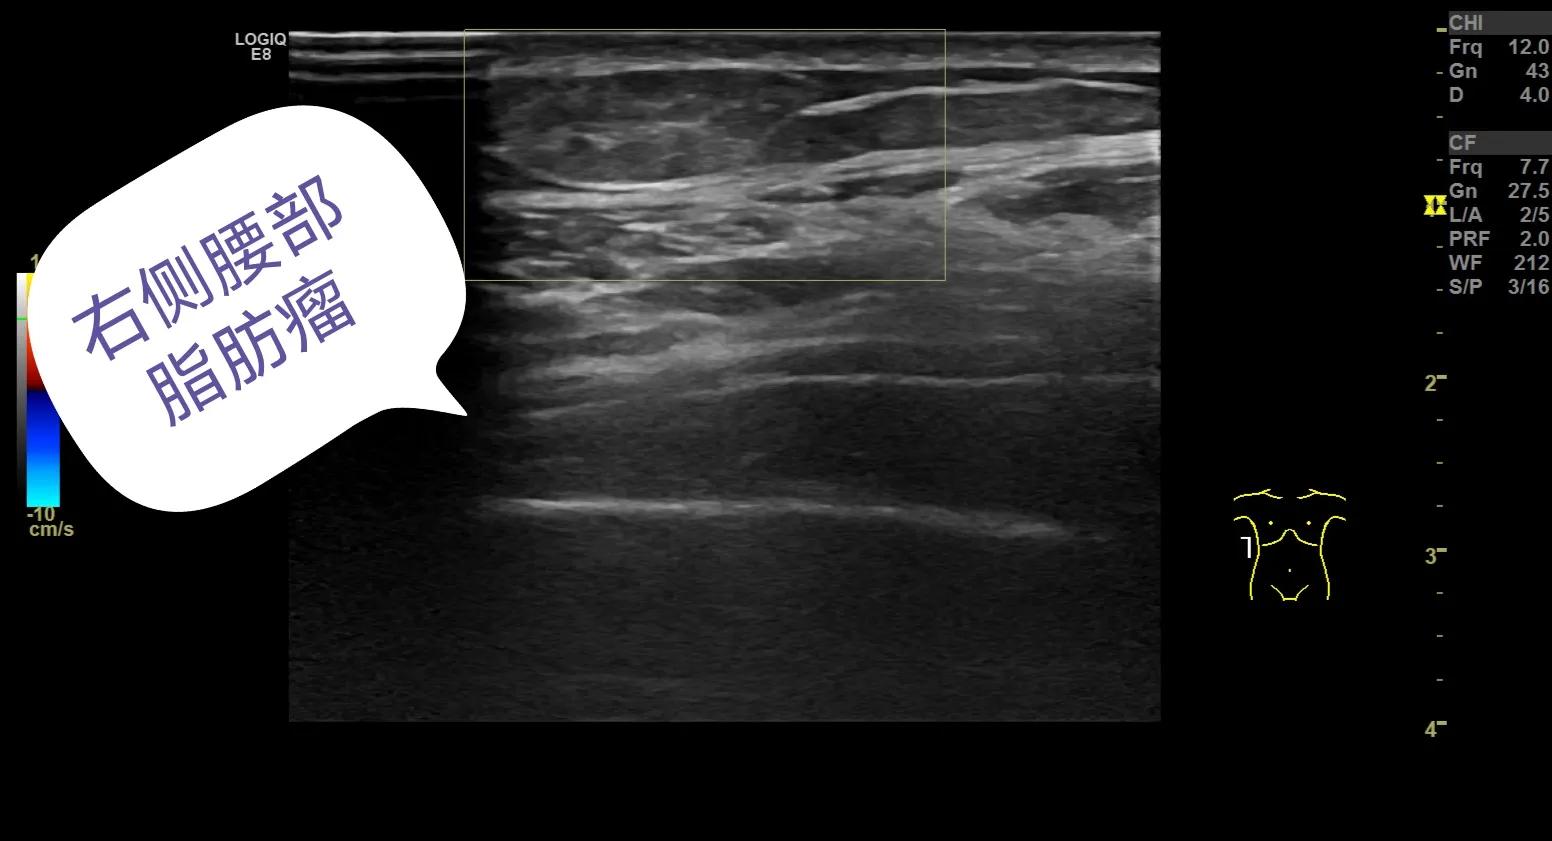

下面给大家分享几个我平时做的病例,发生在各个部位的脂肪瘤。

低回声的脂肪瘤

等回声的脂肪瘤,无血流信号